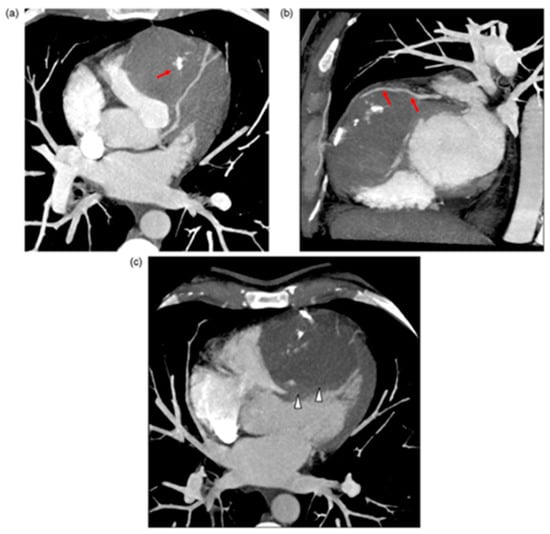

Figure 3.

(A) Electrocardiogram at presentation shows biphasic T wave in lead V3, deep T-wave inversion in leads V4, V5, and V6, and Q waves with T-wave inversion in the inferior leads, consistent with angiographic findings. (B) Coronary angiogram shows moderate stenosis at the proximal segment of the left anterior descending coronary artery, severe stenosis at midsegment, and complete total occlusion in the distal segment. (C–E) Transthoracic two-dimensional echocardiographic and cardiac magnetic resonance views of IDH. (C,D) At presentation, apical four-chamber view showing dissecting echo-free cavity (arrow). (E) An IDH was confirmed by gadolinium-enhanced magnetic resonance imaging, revealing a large thrombus (arrow) within the apical intramyocardial dissection cavity containing the hematoma in the apical segment. Roslan A, et al. CASE (Phila). 2017 August; 1(4): 159–162 [69].

IVS abscess development usually occurs as an extension of infective endocarditis from cardiac valves and is associated with high mortality [70]. Cardiac tumours are some of the rarest primary tumours, while cardiac metastases are more common yet still relatively rare [71]. Seventy-five percent of primary cardiac tumours are benign and seldom involve the IVS. Fibromas and hemangiomas occasionally originate in the IVS and may mimic HCM (Figure 4) [72], whereas hamartomas of mature cardiac myocytes (HMCM) are hyperproliferative growth of mature cardiac cells, which are slow growing and solitary, usually present in young men in their mid-twenties in the ventricles and IVS; they may be asymptomatic.

Figure 4.

(a) Multi-detector computed tomography (MDCT) axial transverse view. Right ventricular (RV) mass occupying the ventricle and bulging out. The mass is pushing out the RV free wall. Note calcifications in the mass (red arrows). (b) MDCT right oblique short axis view. Left anterior descending artery in contact with fibrous mass tissue (arrows). (c) MDCT with multiplanar reconstruction and Maximum Intensity Pixel on four chamber view. Absence of pericardial effusion. The mass is arising from the IVS (white arrowheads); large sessile adherence on IVS. Stéphant E, et al. Eur. J. Radiol. Extra 2008; 67: e103–e106 [72].